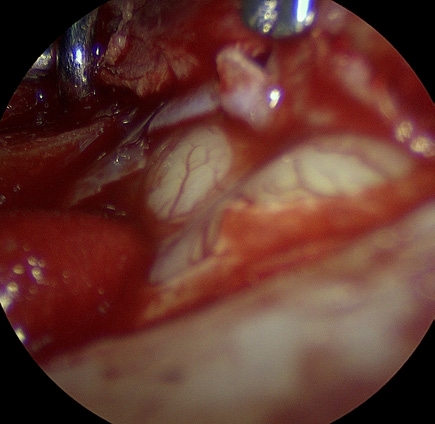

ICG 염색

형광 물질을 이용해 종양 조직과 주변 혈관 구조를 시각적으로 구분하고, 수술 중 판단과 절제 범위 설정을 돕는 기술입니다.

ICG 형광 염색은 수술 현미경과 함께 사용 시 종양과 정상 조직의 경계를 더 명확하게 확인하도록 돕고, 종양 주변 주요 혈관을 식별해 출혈 위험을 줄이며 절제 범위를 보다 정밀하게 설정하는 데 도움을 줄 수 있습니다.

정상 뇌 조직과 종양 경계가 모호한 경우, 정확한 절제와 기능 보존을 함께 고려한 수술 계획에 유용합니다.

ICG 염색 수술 이미지

수술 이미지

ICG 형광 확인 이미지

형광 확인